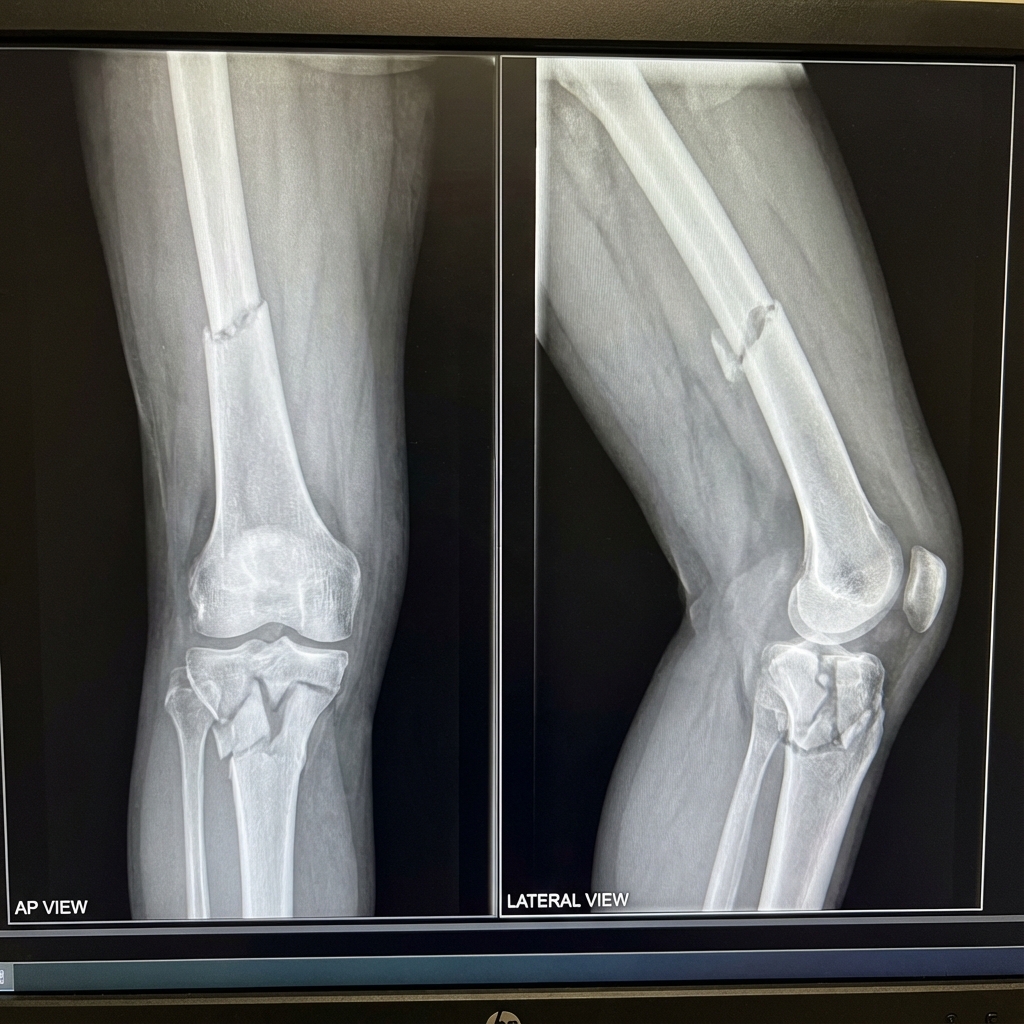

AP and lateral radiographs of the left leg showing ipsilateral displaced femoral shaft fracture (mid-diaphysis, transverse) and comminuted tibial plateau fracture. The knee is 'floating' without bony stability above or below.